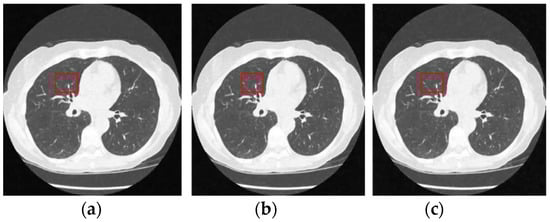

Figure 12 and Figure 13 analyze the region of 45 × 45 that has been considered to be the upper right area of the center in a region containing all types of details, including edges, shade gradient, and extremities, in contrast values. This region was mapped in the same area for all the noisy and denoised CT images using built-in MATLAB functions. Post this, magnification shows the edge reconstruction and contrast restorative properties of this framework in grandiose detail in Figure 14. The white regions of details are visible with a high level of clarity in the denoised CT images in Figure 14. The Gaussian noise is also clearly visible in the magnified view, as seen in Figure 14a–c. The recovery from Figure 14c is beyond the capability of any human expert, which is done flawlessly by the system.

Figure 12.

Noisy CT images with various noise variance levels (a) 1% Gaussian noise, (b) 1.5% Gaussian noise, and (c) 2% Gaussian noise.

Figure 13.

Denoised CT images generated via proposed technique: Marked region used for zooming analysis; (a) denoised on 1% Gaussian noise, (b) denoised on 1.5% Gaussian noise, and (c) denoised on 2% Gaussian noise.

Figure 14.

Comparison of the marked region from noisy and denoised CT images: Zooming analysis of the marked region. (a) 1% Gaussian noise, (b) 1.5% Gaussian noise, and (c) 2% Gaussian noise.